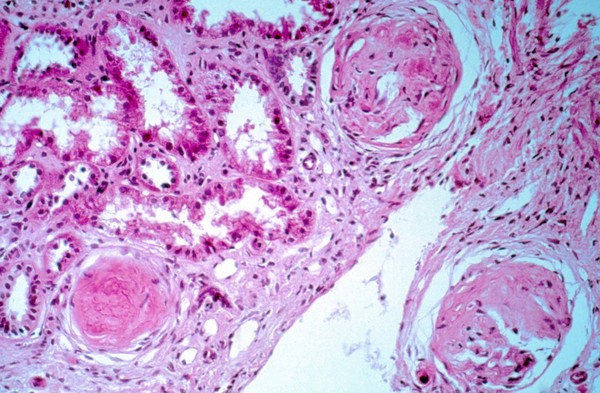

Diffuse lepromatous leprosy: Lucio phenomenon

Leprosy: kidney